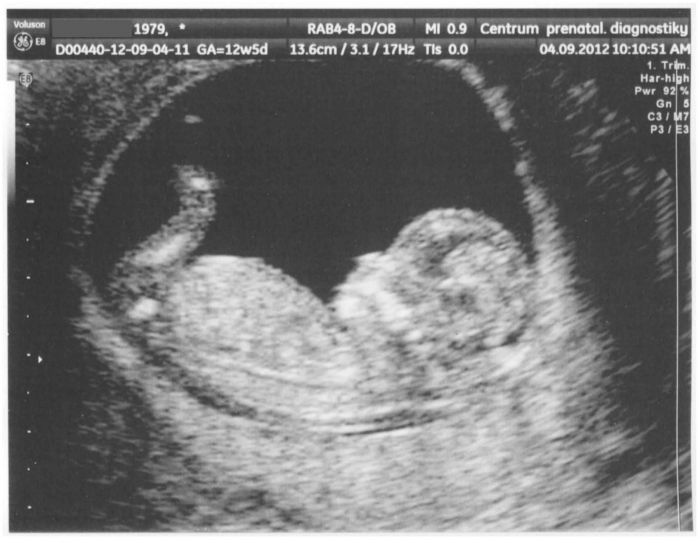

Holky, tak mám ten I. screening taky za sebou. Mimi je v pořádku a musím říct, že ultrazvuk byl nádherný. Draly se mi do očí i trochu slzy, bylo to krásné. Kdo tam ještě nebyl, je to jen o krvi a břišním ultrazvuku - nic jiného. Já jsem byla v Brně v Centru prenatální diagnostiky. Všichni byli moc příjemní. Krev i ultrazvuk mi dělali v jeden den. Při UZ jsem měla nad sebou velkou obrazovku, kde se mimi promítalo barevně. Pěkně si tam hraje..

Pohlaví vůbec vidět nebylo. Byla jsem tam v 10 ráno a už ve 14 hodin mi volali výsledky, navíc je to po dobu 30 dnů i na jejich stránkách. Jinak jsem tam jela z Prahy a všechno jsem měla tak akurát na čas, tak jsem nestihla ani wc, tam mě upozornili, že je UZ lepší s plným měchýřem, tak jsem to držela dál. MUDr. přes tak plný močák ale nemohla provést vyšetření pořádně, tak jsem si musela odskočit a pak jsme zase musely asi 5 minut čekat, až se mimi správně natočí. Bylo moc milé, jak k němu MUDr. rozmlouvala a přemlouvala ho..

Nakonec mi řekla, že je vše v pořádku a že mám krásné miminko, no to mě úplně dojala. Na schodech při odchodu se mi chtělo fakt brečet, byla jsem tak šťastná..

Miminko je nádherné!!

Mimi je kouzelné

Koukám, že mrňousek je také pěkné šídlo, vyplazuje si jazýček - co si asi v tu chvíli myslí